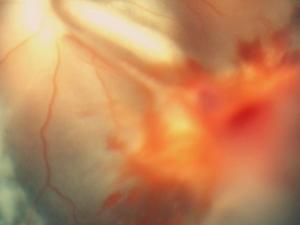

El envejecimiento es un proceso derivado de la disminución de la regulación genética en el interior de las células, ya sean cerebrales, células madre hematopoyéticas o células pancreáticas